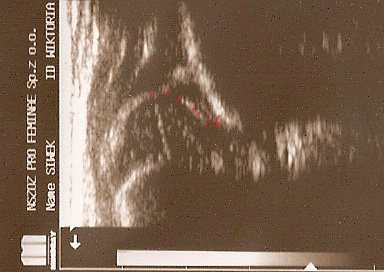

typIIa 6tyg.ż. dach kostny wystarczajacy;brzeg kostny kanciasty(mimo dysplastycznej panewki) pierwsza część dachu dobra ,

druga głębsza stroma(trzeba na to uważać) ;dach chrzestny pokrywa

górne zdjęcia strzałki pokazują obrabek(czerwona):brzeg kostny (żółta);gałąż dolna(niebieska) ,

prawidłowy przebieg linii dachu kostnego(niebieska) stycznie do echa gałęzie dolnej i echa brzegu kostnego ;

linii dachu chrzęstnego (czerwona) stycznie do brzegu kostnego i przez środek geometryczny obrąbka i

linii podstawnej ( żółtarównolegle do sylwetki kości biodrowej po zewnetrznej stronie prze punkt gdzie ochrzęstne przechodzi w okostna i styka sie z echem kości

dolny staw prawidłowy Typ I dach kostny dobry;brzeg kostny tępy ;dach chrzestny pokrywa

dolne zdjęcia strzałki pokazują obrabek(czerwona):brzeg kostny (żółta);gałąż dolna(niebieska) ,

linii podstawnej ( żółta

typIIa 4yg.ż. dach kostny wystarczajacy;brzeg kostny okragły;dach chrzestny pokrywa

linii podstawnej ( żółta)równolegle do sylwetki kości biodrowej po zewnetrznej stronie

przez punkt gdzie ochrzęstne przechodzi w okostna i styka sie z echem kości

typ II/ D powyżej 4tyg.ż. dach kostny bardzo niewystarczajacy;brzeg kostny spłaszczony

;dach chrzestny przesunięty dogłowowow ( szczyt głowy jest poniżej szczytu dachu chrzęśtnego)

linii podstawnej ( żółta)równolegle do sylwetki kości biodrowej po zewnetrznej stronie prze punkt gdzie ochrzęstne przechodzi w okostna i styka sie z echem kości : w przypadku wysuwania głowy z panewki nie zawsze jest to już pozycja standardowa; sylwetka kosći biodrowej pochyla sie i powiniśmy kreślic linie zgodnie z odchyleniem w lewo druga żółta liinia kropkowana ( trzeba o tym pamiętac bo z D wykreślimy I prawidłowy kąt @ o wartości 62 st .I jest to najczęstszy błąd; u kikutygodniowych niemowląt kiedy zmiany wtórne nie sa jeszcze wykształcone; o poważnych konsekwencjach zwłaszcza jeśli korzystamy z programów do automatycznego wykreslania kątów )